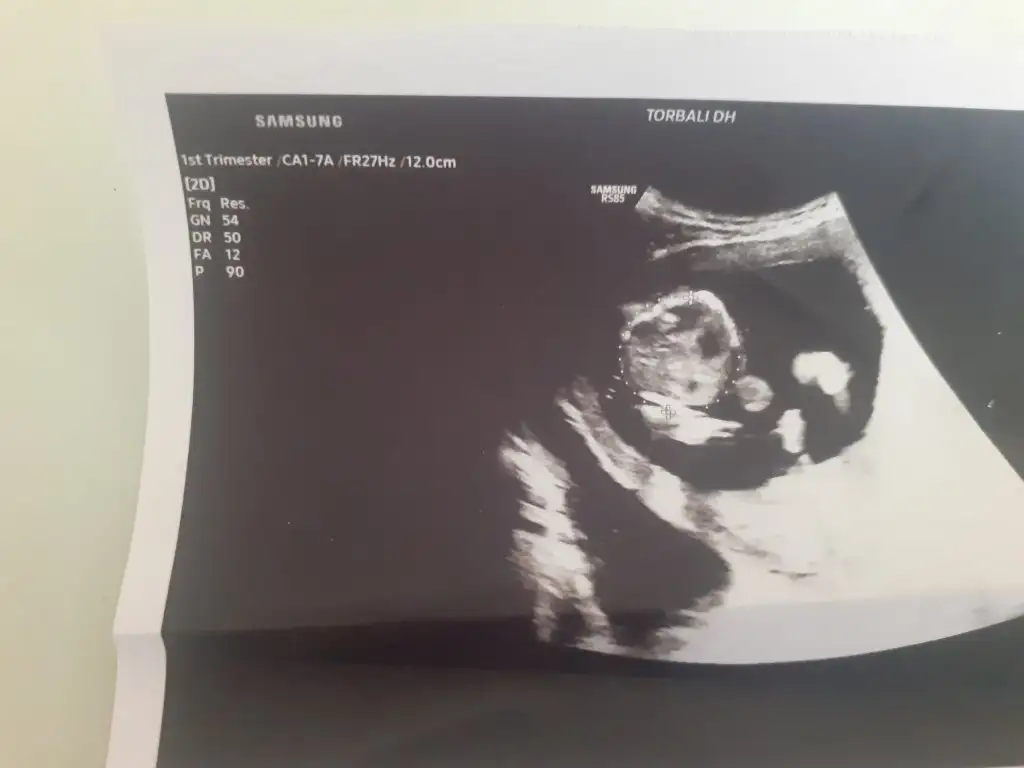

Evet burda gerçekten tam bir prensesDoktor kız dedii![]()

prenses gibi9+3 karından bakabilir misiniz?